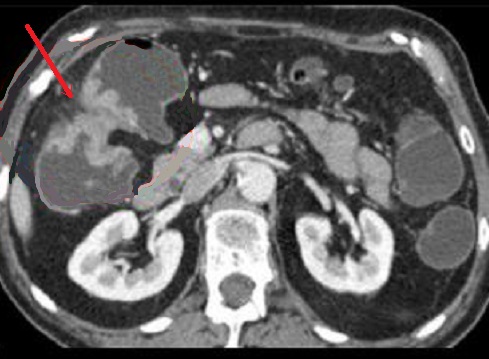

La TDM technique de tres frequemment d'utilise pour explore

des tumeur colo-rectale et les metastase . Aspect

radiologique frequemment est image de stenose irreguliere

d'une portion du colon , ou aspect stenosant en " trognon de

pomme " . Au caecum a spect radiologique parfoi est image en

laculaire ou bourgeonnante .

Aspect stenosant

d'une adenacarcinoma de anglecolique droit du colon

( fleche rouge ) . C'est image de epaissisement

stenosant symetrique a hyperdense d'une portion du

colon avec bord tres irrgulierement ( stenose

ireguliere) . Image

radiologique du colo CT a l'eau , coupe axiale |